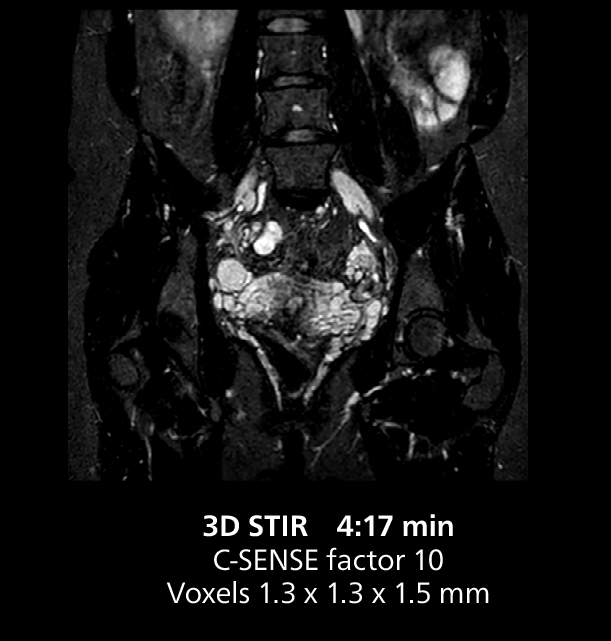

The isotropic high resolution 3D sequence in this MRI case allows for reformatting to obtain other orientations with high quality. Acquired on the MR 5300 system.

Dr. Gellée highlights the robust free-breathing scans as “the feature that makes the biggest difference in my daily work. The 3D free breathing sequences are very reproducible, and the axial acquisition is very good. For example, in endometriosis, which is one of my focus areas, it provides high contrast and good resolution so that I can see small details. We also use free breathing for liver and pancreas imaging. In multi-phase liver studies, 4D Free Breathing delivers 3-second temporal resolution, making a dynamic scan with more than one arterial phase possible.”

The MR 5300 with Compressed SENSE is up to 50%** faster for many exams. It can provide routine exams in less than 5 minutes and whole-body exams in less than 20 minutes. Saint-Augustin has taken advantage of that speed to create highly efficient protocols. The hospital’s standard stroke protocol is just about 8 minutes, and standard ENT, prostate PIRADS staging, and endometriosis studies all clock in at just about 10 minutes.***